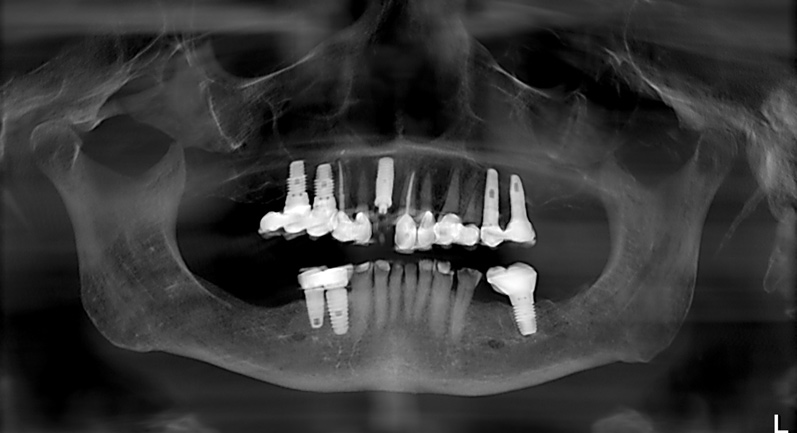

Fig 12. Preoperative radiograph revealed the location and spacing of previously placed implants.

Figure 12